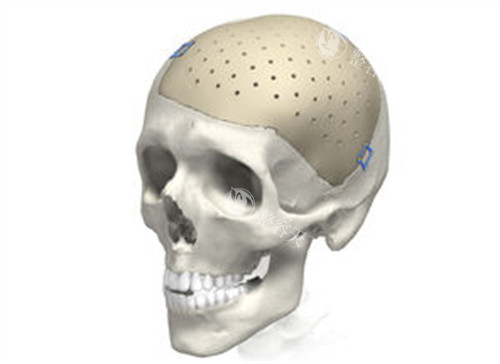

上海时光在 peek 颅骨修补这块,较让人放心的就是它的 3D 打印技术。

术前会给患者做详细的 CT 扫描,把颅骨缺损的情况比较准还原成 3D 模型。医生根据这个模型来定制 peek 材料,能做到和原来的颅骨严丝合缝,术后外形看起来特别自然。